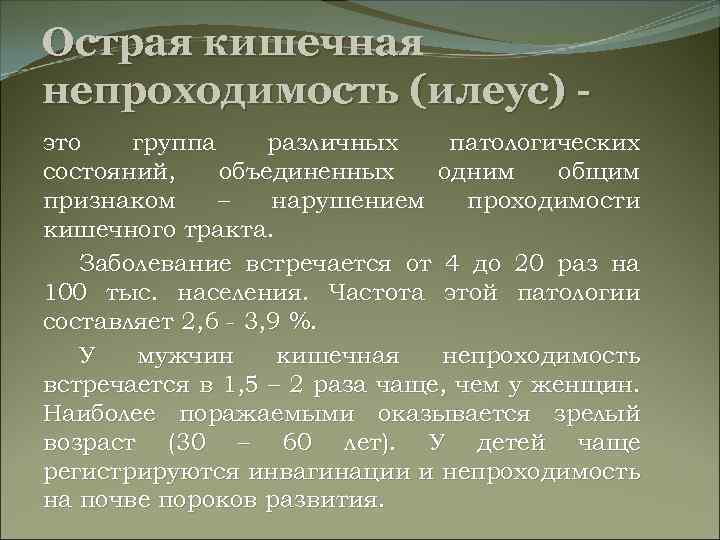

Иллюстрации и информация о симптомах острого кишечного непроходимости